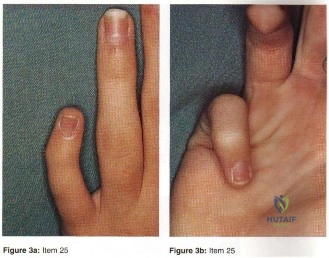

- Clinodactyly

- Camptodactyly

- Symbrachtyly

- Kirner’s deformity

- Digiti minimi adductus

- Clinodactyly

- Camptodactyly

- Symbrachtyly

- Kirner’s deformity

- Digiti minimi adductus